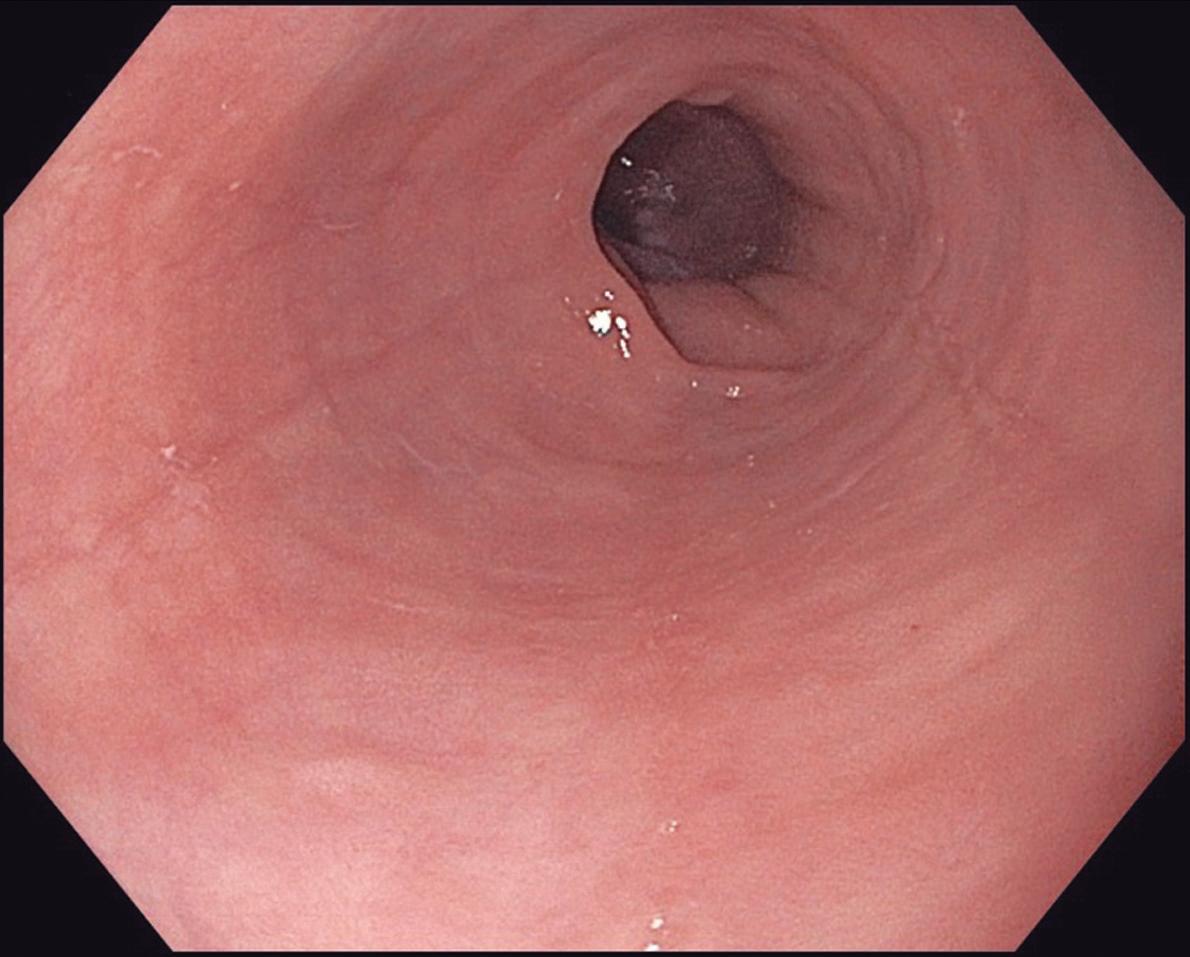

Evaluación endoscópica e histológica

La endoscopía superior es un procedimiento fundamental para el diagnóstico, la evaluación de la respuesta al tratamiento y el monitoreo a largo plazo de la actividad de la EEo. Los hallazgos endoscópicos típicos incluyen edema (reducción de vascularidad), anillos esofágicos fijos, exudados blancos, surcos longitudinales, estenosis, estrechamiento de la luz esofágica, friabilidad de la mucosa (mucosa en papel crepé) y una consistencia firme de la mucosa al realizar biopsias (signo de “tracción" o "resistencia”) en pacientes con fibrosis (Figura 1). Estos hallazgos no son patognomónicos y no constituyen un criterio diagnóstico; sin embargo, cuando se evalúa de forma cuidadosa, en la gran mayoría de los casos se pueden observar.19-21

En el panel A se observa un esófago con edema difuso y pliegues longitudinales; en el panel B se aprecia edema con pliegues y exudados blanquecinos; en el panel C se evidencia un estrechamiento luminal acompañado de anillos esofágicos y exudados; y en el panel D se muestra un desgarro mucoso posterior a la dilatación con bujía de Savary, hallazgo esperado tras este procedimiento terapéutico.

Figura 1. Características endoscópicas de la esofagitis eosinofílica